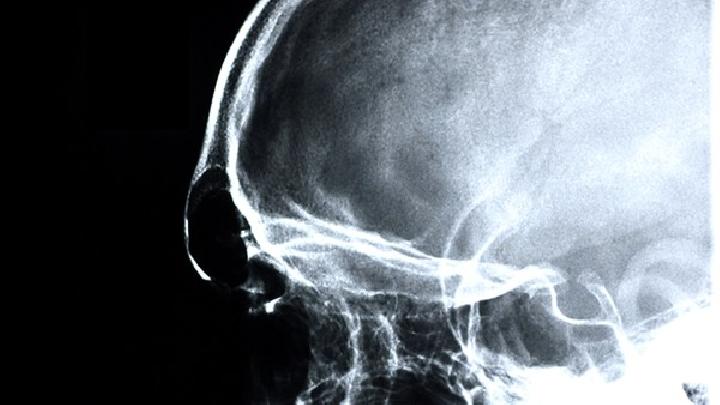

颈椎病手指麻怎么回事?

颈椎病手指麻可能由神经根受压、椎间盘突出、颈椎退行性变、颈椎不稳、局部血液循环障碍等原因引起,颈椎病手指麻可通过药物治疗、物理治疗、牵引治疗、手术治疗、生活方式调整等方式治疗。1、神经根受压 颈椎病导致神经根受压时,可能引发手指麻木。神经根受压可能与...